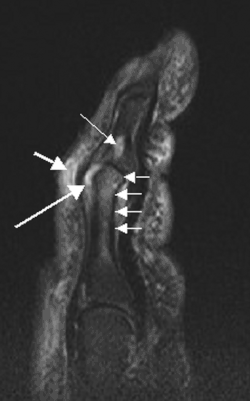

- Дактилит — это острое или хроническое воспаление пальца, клинически проявляющееся болью, цианотическим окрашиванием пальцев, плотным отеком пальцев, болевым ограничением сгибания, характерной для псориатического артрита сосискообразной деформацей пальцев. Является типичным признаком псориатического артрита, возникающий в результате одновременного поражения сгибателей и (или) разгибателей пальцев, а также артрита межфаланговых суставов. Может явиться результатом ногтоеды, когда воспаление распространяется с окружности ногтя дальше по клетчатке, сухожильным влагалищам мышц пальца и по надкостнице пальца[5].

- Теносиновит проявляется болью, припуханием по ходу сухожилий, а также ограничением функции (сгибание пальцев).